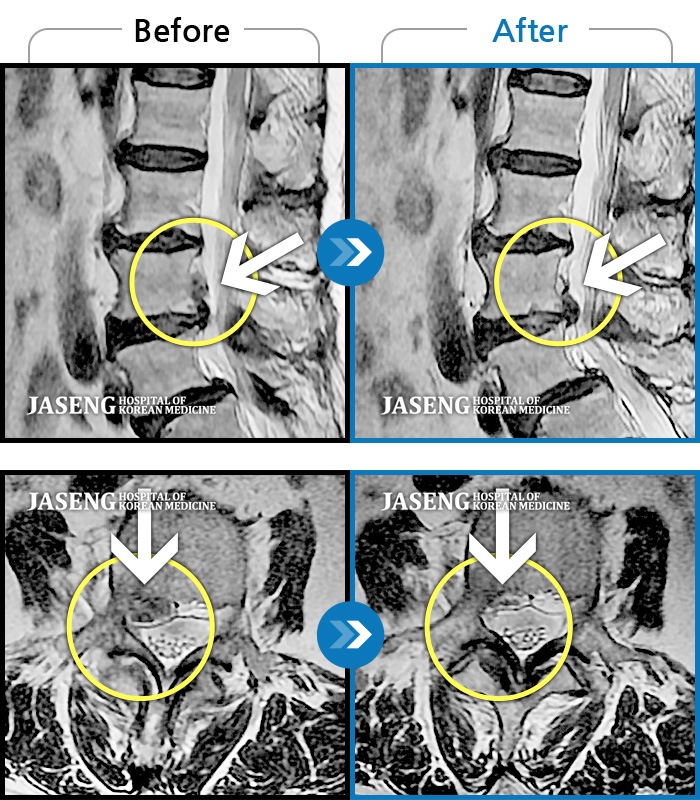

MRI 치료사례

우측 허리와 골반이 아프고, 우측 하지 후면으로 통증이 있다.